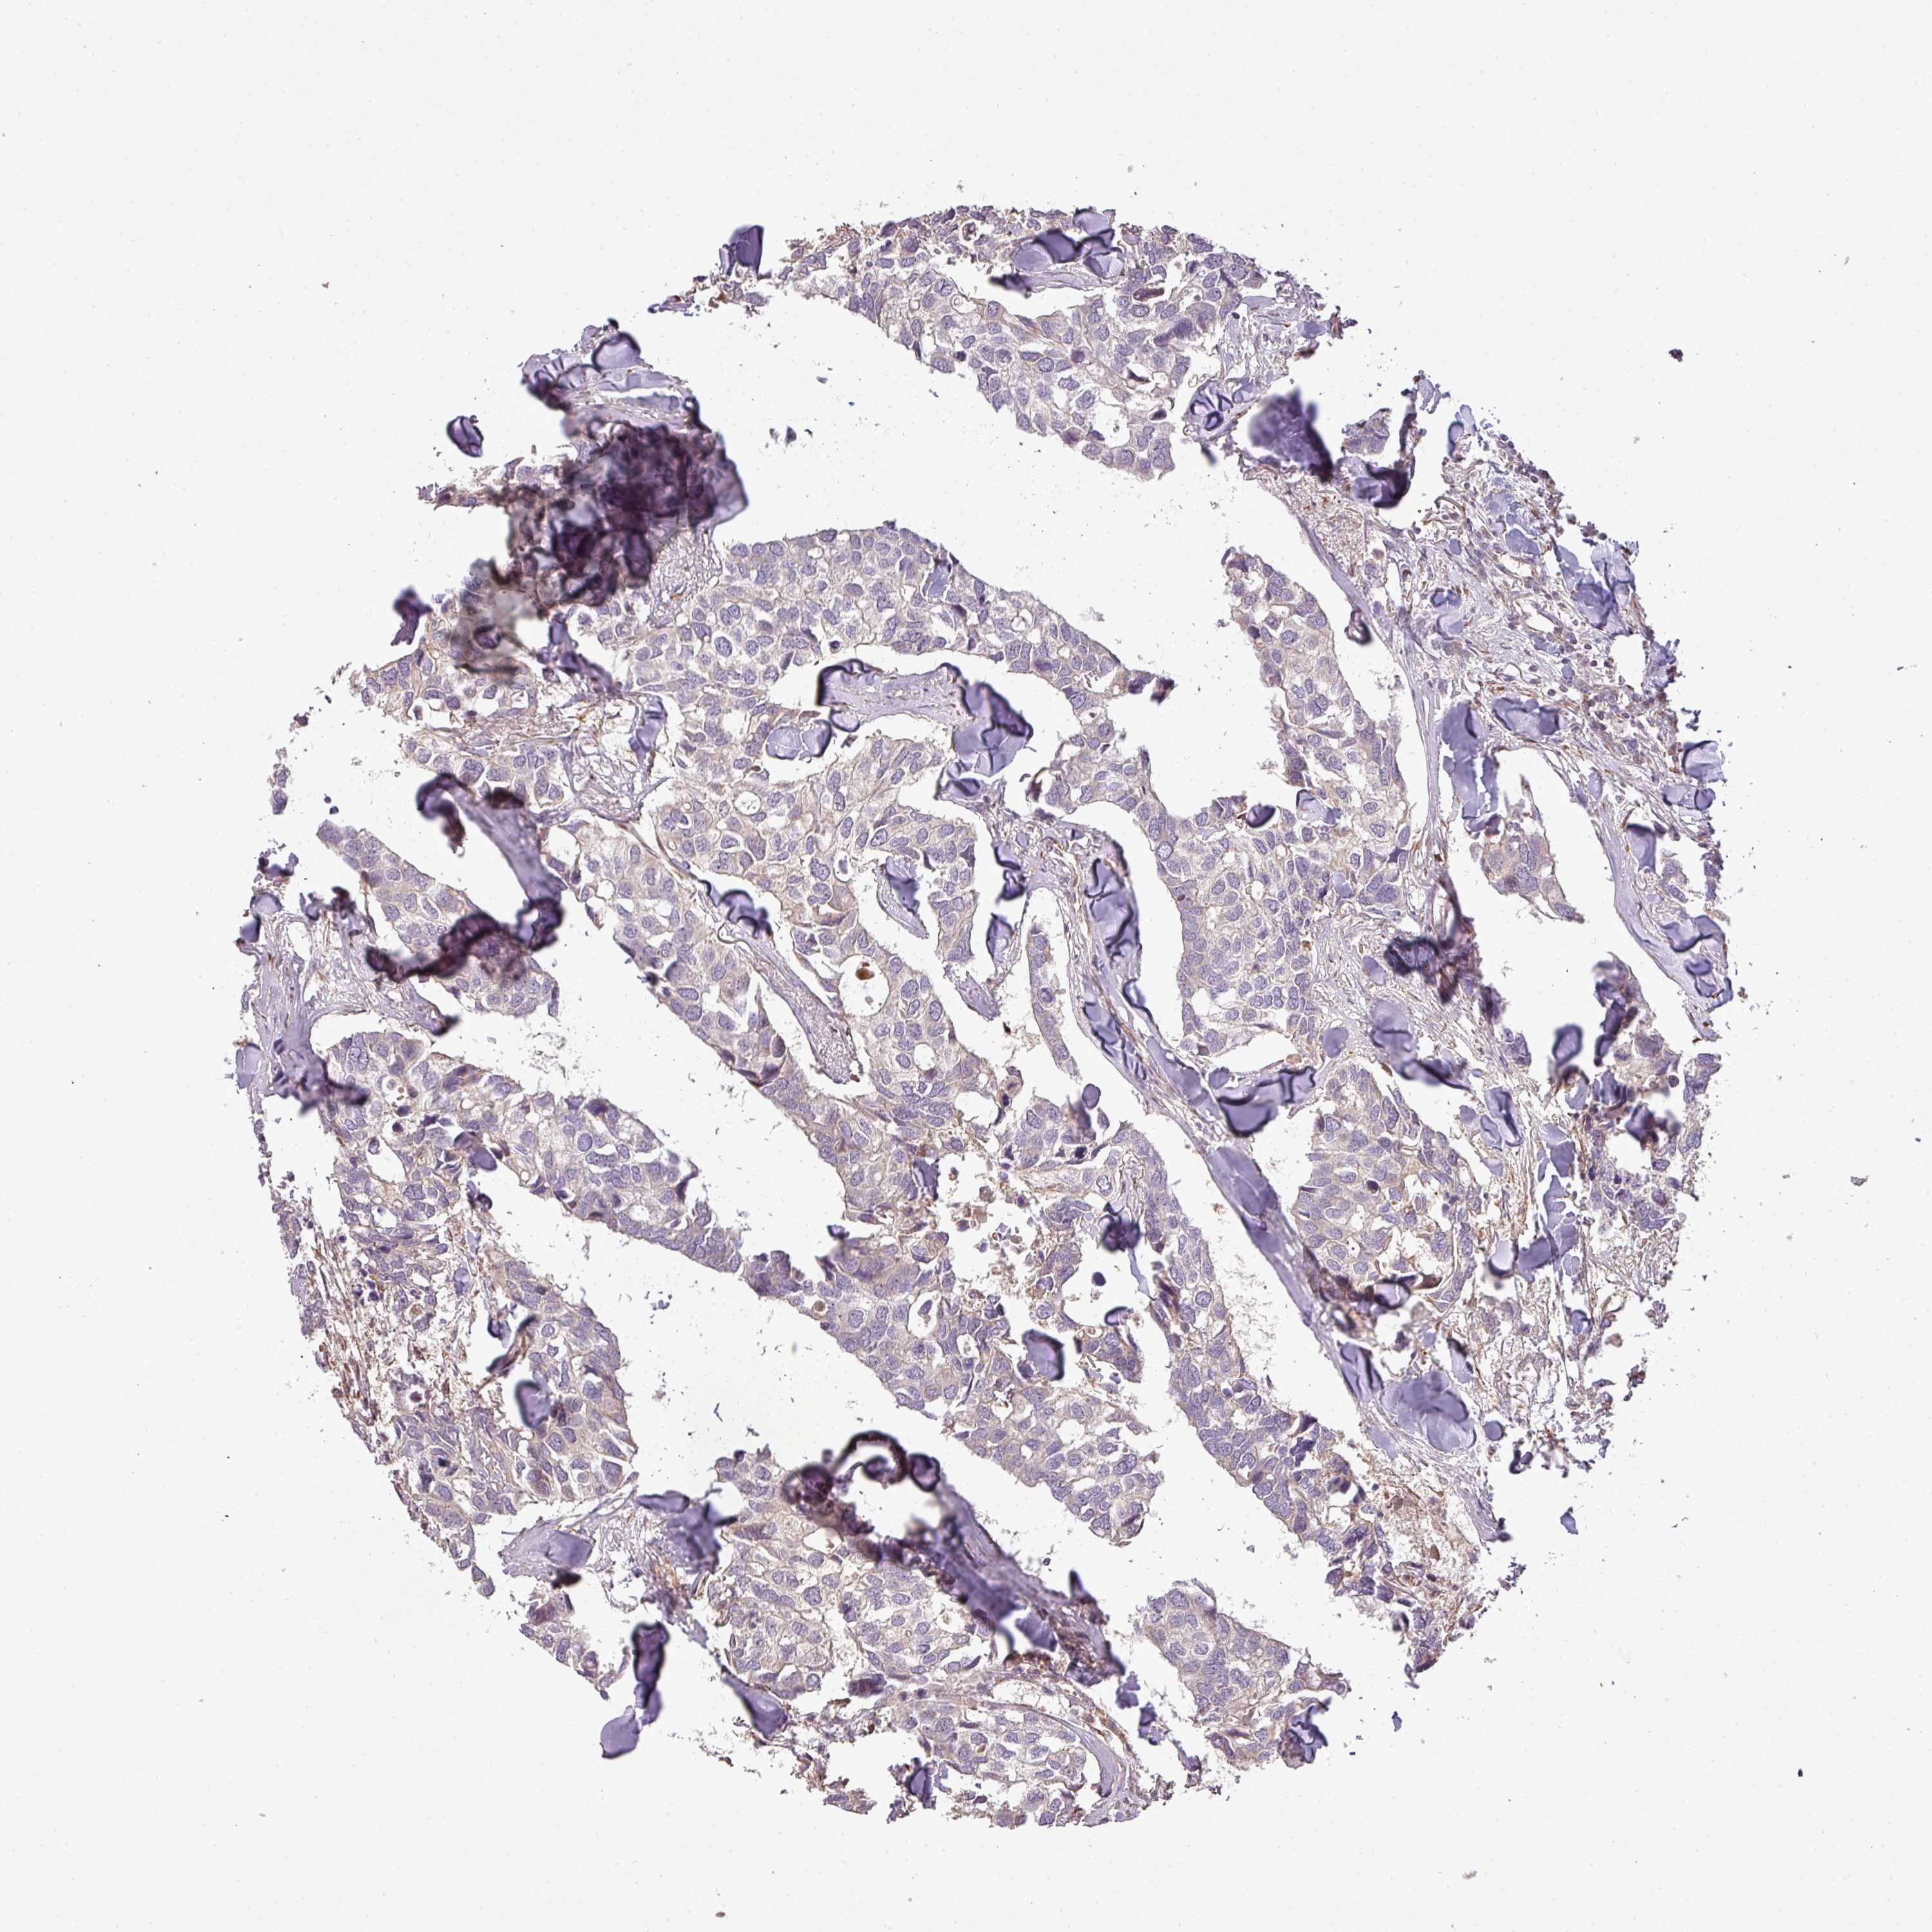

CANCER BREAST CANCER Show tissue menu

BRCA TCGA BRCA VALIDATION PROTEIN EXPRESSION